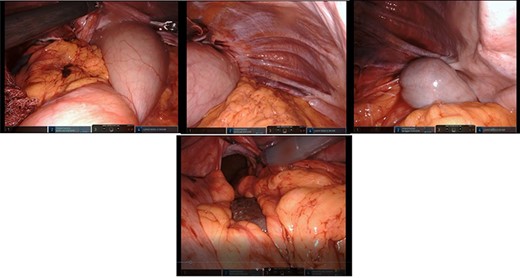

After mobilization of the left liver lobe, visualization of the hiatus was achieved. A two silk suture was placed through the avascular hepatogastric ligament and outside the patient’s anterior abdomen with an extracorporeal knot in order to assure atraumatic elevation-retraction of the liver. Space was created in the surgical field due to the absence of a retracting surgical instrument within the abdominal cavity. The hernia’s sac was then dissected with use of energy device and bipolar cautery with minimal traumatic tissue handling; the herniated stomach, transverse and left colon, omentum and finally spleen were dissected free (Fig. 2). Due to the atypical clinical symptomatology as well as increased PLT, the suspicion of chronic ischemia of the herniated organs was raised. ICG was administered to assess the patency of blood supply in the herniated organs and specially to the spleen; blood supply was excellent and as a result, no further resections were needed (Fig. 3). An 8- × 4-cm posterolateral diaphragmatic defect was revealed; the defect was repaired with the use of ProGrip mesh and was supported by a continuous V-loc suture for fixation. The patient resuscitated from anesthesia in great condition and returned to the ward, with an uneventful course. A post-operative upper GI fluoroscopy was conducted at the second post-operative day (POD), and oral diet was commenced (Fig. 4).

Upper GI fluoroscopy to assess the results of the hernia repair during the third POD.